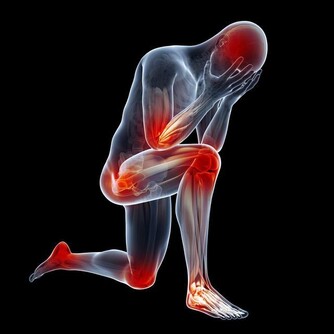

夏天雨水多,且多陣雨、暴雨,如果不能很好的防護躲避,硬冒雨涉水前行並滯留時間過長,很容易使得寒濕之氣進入人體,損傷陽氣,而患發熱、腹瀉、嘔吐等疾患,同時也為風濕性關節炎、類風濕性關節炎等疾病埋下病根。

《素問·生氣通天論》中指出“陽氣者,煩勞則張”、《素問·舉痛論》中說到“勞則氣耗”,過度的體力、腦力勞動以及房勞會耗氣傷陽,造成肢體倦怠、精神不振、表情淡漠、不思飲食、頻頻欲睡等,因此勞逸結合,動以養形,靜以養神有利於身體健康。